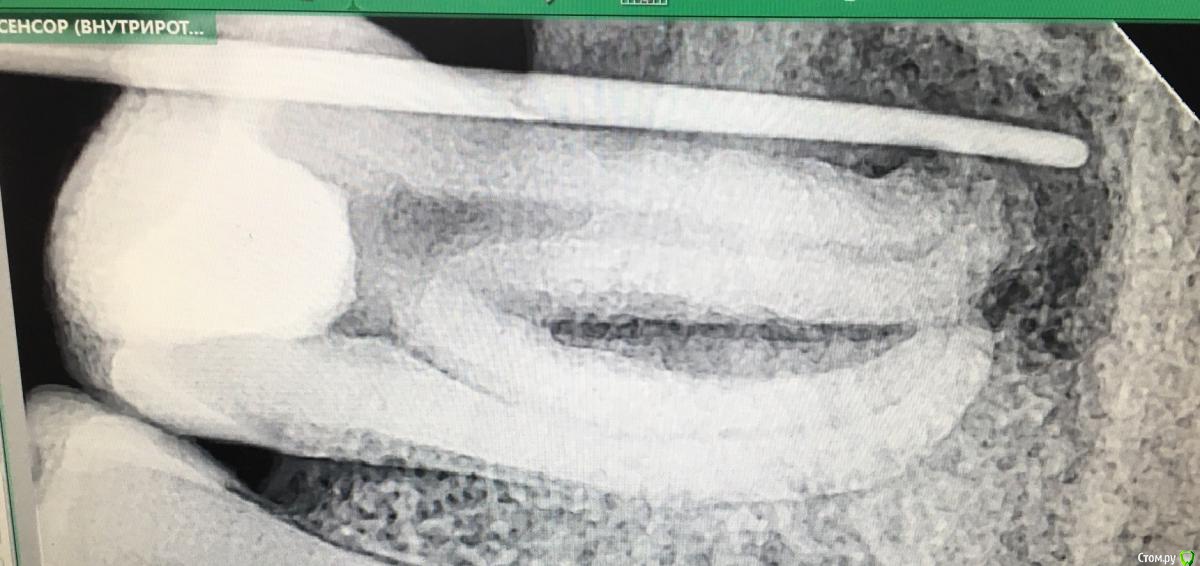

kuziy12 Опубликовано 17 мая, 2019 Автор Поделиться Опубликовано 17 мая, 2019 Начал осваивать фотоаппарат, но пока хрень выходит, так что рентген снимки - one love. 3.7 Жалобы: боли при накусывании. Анамнез: боли появились 2 дня назад. Объективно:-Подвижность 2 степени-Сопр без изменений-Перкуссия резко болезненна-Небольшая кп на окклюзионной Отправляю на диагностический снимок(его не сфотал) - разряжение в области дистального. Ставлю диагноз - обострение хрон. периодонтита. Начинаю препарировать, а там нерв. Живой. Смотрит на меня и говорит: Хрен ли надо? Я в этот момент: Начинаем разбираться и выясняется: Итог: Вестибулярной нет вообще. Зуб удален. Сам пациент связывает с удалением 3.8 полтора года назад с помощь долота и молота. Вывод: Хорошая диагностика сокращает лишние телодвижения. 1 Ссылка на комментарий